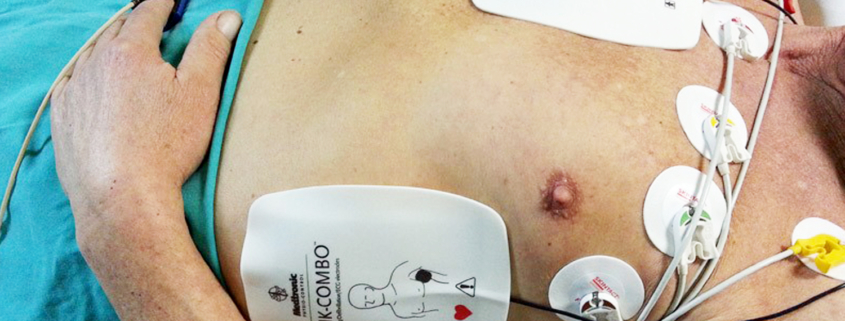

Privremeni elektrostimulator srca (ES) uključuje stimulaciju srca uslijed najčešće sporog srčanog rada (bradikardije) ili rjeđe brzog srčanog rada (tahikardije), kraće vrijeme dok se ne ukloni uzrok nastajanja poremećaja srčanog ritma ili do ugradnje trajnog elektrostimulatora.